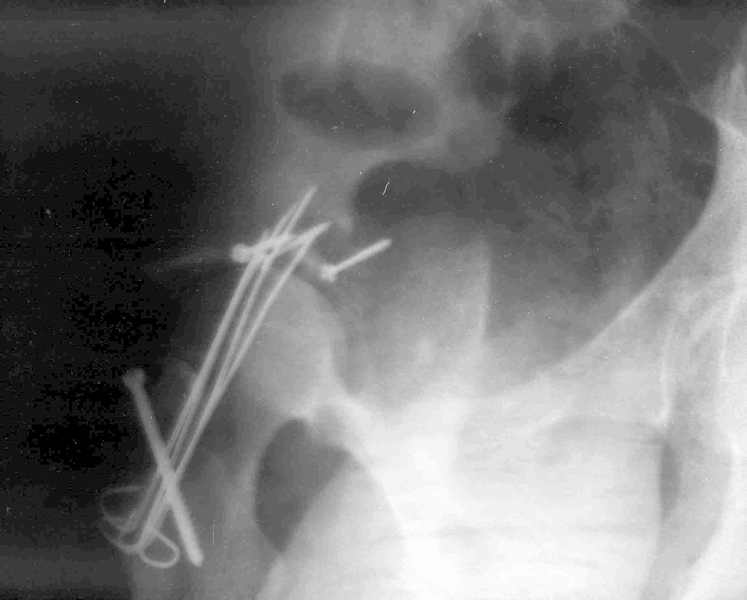

Мужчина 32 года, автотравма 6 недель назад. При поступлении был установлен диагноз "Ацетабулярный перелом". Вывих бедра не был установлен.

После установления вывиха бедра через 3 недели после травмы больному выполнена попытка открытой репозиции, остеосинтез вертлюжной впадины, Бедро фииксировано трансартикулярно спицами. После операции неврит седалищного нерва. В течение ещё 3-х недель после операции установлено что отломки не репонированы, вывих бедра не устранён (см. КТ и рентгенограмму), неврологической динамики нет. Возние вопрос о повторном оперативном вмешательстве по поводу чего разгорелись жаркие споры и сформировалось следующие мнения:1. Тотальное эндопротезирование с цементной фиксацией чашки протезом "ЭСИ" (другого протеза нет)2. Повторная открытая репозиция бедра с замещением дефектов вертлюжной впадины аутокостью с целью подготовки для последующего эндопротезирование. Предполагается фиксация тазобедренного сустава в послеоперационном периоде гипсовой повязкой или аппаратом внешней фиксации.Прошу высказать ваше мнение о тактике дальнейшего лечения пациента, о предложенных вариантах. Отдельный вопрос о возможности первичного тотального эндопротезирования при ацетабулярных переломах. (Лечащий врач настаивал перед первой операцией на выполнении тотального эндопротезирование с цементной фиксацией чашки через 3 недели после травмы)

Было бы существенным посмотреть обзорную R-грамму до операции. По данным послеоперационных снимков и КТ имеется низкий двухколонный перелом или

высокий Т-образный перелом с отрывом свода. Для уточнения необходиы косые проекции (Judet). Весь ли седалищный нерв молчит или только м/б порция?

Высылаю прямой обзорный и косой подвзошный снимки, косой запирательный неудовлетворительного качества.